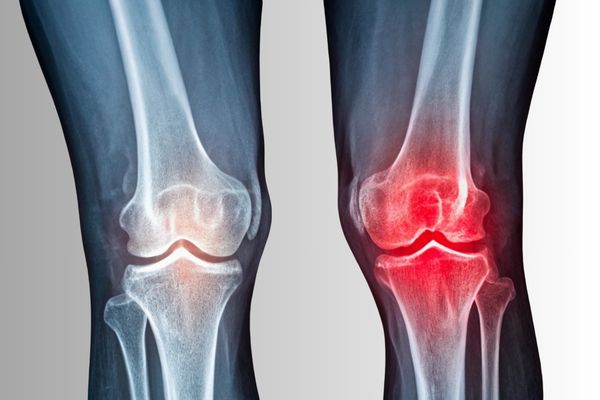

Zjednodušeně řečeno jde o proces opotřebení chrupavky v kloubu. Tato chrupavka funguje jako přirozený „tlumič“ mezi kostmi – umožňuje hladký a bezbolestný pohyb.

Jakmile se začne ztenčovat nebo zcela ztrácet, kosti se o sebe třou, vzniká bolest, zánět, otok a omezená hybnost.

3️⃣ Fáze – zánět a strukturální změny

Pokud tělo dlouhodobě nezvládá přetížení a odpadní látky se nestačí vylučovat, přidává se zánět. Kloub otokne, hřeje, někdy se objeví zarudnutí – tělo zvyšuje průtok krve v místě, aby mohlo opravit poškození. Jenže bez výživy, regenerace a správného vnitřního prostředí to nestačí.

Na rentgenu už bývají viditelné úzké kloubní štěrbiny, výrůstky (osteofyty) nebo deformace kloubu. Bolest je stále výraznější a pohyb omezenější.